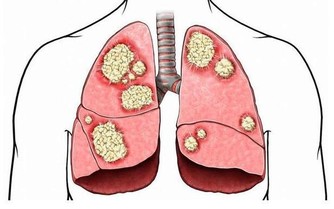

二、無法治癒的腳掌疼痛

糖尿病患者的血糖濃度升高會導致腳部神經的破壞,具體表現就是經常會發生由於壓力或不小心的摩擦而引起切傷、刮傷或刺激。如果您發現您的腳掌經常疼痛,那麼您需要仔細留意一下,您的足底皮膚是不是會紅腫、皸裂、長水皰、腳癬及腳趾變形等症狀。如果有上述的一部分症狀,您就需要去醫院檢查一下您的血糖是否已經很高了。

對於高血糖的朋友來說,每天用溫和的中性肥皂水洗腳很有必要的,而且洗腳時水溫應在35℃為宜,水溫不能過高,因為會對糖尿病患者造成腳部傷害。同時,浸泡腳的時間不能太長,只要20-30分鐘就可以了。洗腳之後要用純棉毛巾輕輕擦腳,以免造成腳部損傷。